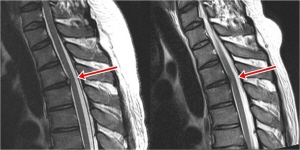

ÈäÃß µð½ºÅ©´Â °ÅÀÇ ¾ø´Ù´Â ÀÇ»çÀÇ ¼³¸í°ú´Â ´Þ¸® Á¤¾¾ÀÇ ÈäºÎ MRI¿¡¼­ ÈäÃß 3¹ø°ú 4¹ø »çÀÌ, 6¹ø°ú 7¹ø »çÀÌ¿¡ ¹Ì¼¼ÇÑ µð½ºÅ© Å»ÃâÁõÀÌ ¹ß°ßµÆ´Ù. ±×·¯³ª ÀÏ¹Ý º´¿ø¿¡¼­´Â Çϳª°°ÀÌ ½Å°æ ¾µ Á¤µµ°¡ ¾Æ´Ï¸ç Áö±ÝÀÇ Áõ»ó°ú´Â »ó°ü¾ø´Ù´Â ´ë´ä¸¸ ÇÒ »Ó Ä¡·á¿¡´Â ȸÀÇÀûÀ̾ú´Ù.

MRI »ó¿¡¼­ ÈäÃß µð½ºÅ© Å»ÃâÁõÀÌ ÀÖ´Ù°í ÇØµµ °¨º°À» À§ÇØ ÇÊ¿äÇÑ °Ë»ç°¡ ÇÑ °¡Áö ´õ ÀÖ´Ù. µð½ºÅ©°¡ Æ¢¾î³ª¿Â ºÎÀ§¿¡ ÁÖ»ç·Î ¾à¹°À» Åõ¿©Çؼ­ Æò¼ÒÀÇ Áõ»ó º¯È­¸¦ °üÂûÇÏ´Â °ÍÀÌ´Ù. Æ¢¾î³ª¿Â µð½ºÅ©°¡ ¿øÀÎÀ̶ó¸é È¿°ú°¡ ¹Ù·Î ³ªÅ¸³ª±â ¶§¹®¿¡ Áø´ÜÀÌ º¸´Ù Á¤È®ÇØÁø´Ù. ¶ÇÇÑ ½ÉÇÏÁö ¾ÊÀº Á¤µµÀÇ µð½ºÅ© Å»ÃâÁõÀ̶ó¸é ÁÖ»çÄ¡·á¸¸À¸·Îµµ Áõ»óÀÌ °³¼±µÉ ¼ö ÀÖ¾î È¿°úÀûÀÎ Ä¡·á¹ýÀÌ µÈ´Ù.